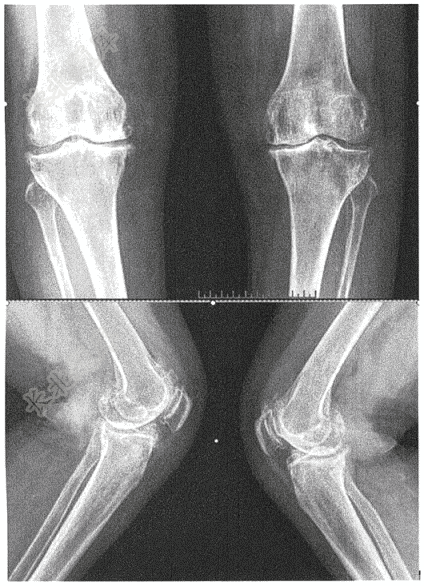

- 简答题女,63岁,双膝活动后疼痛,有响声3年,请判读下方是什么部位,什么项目